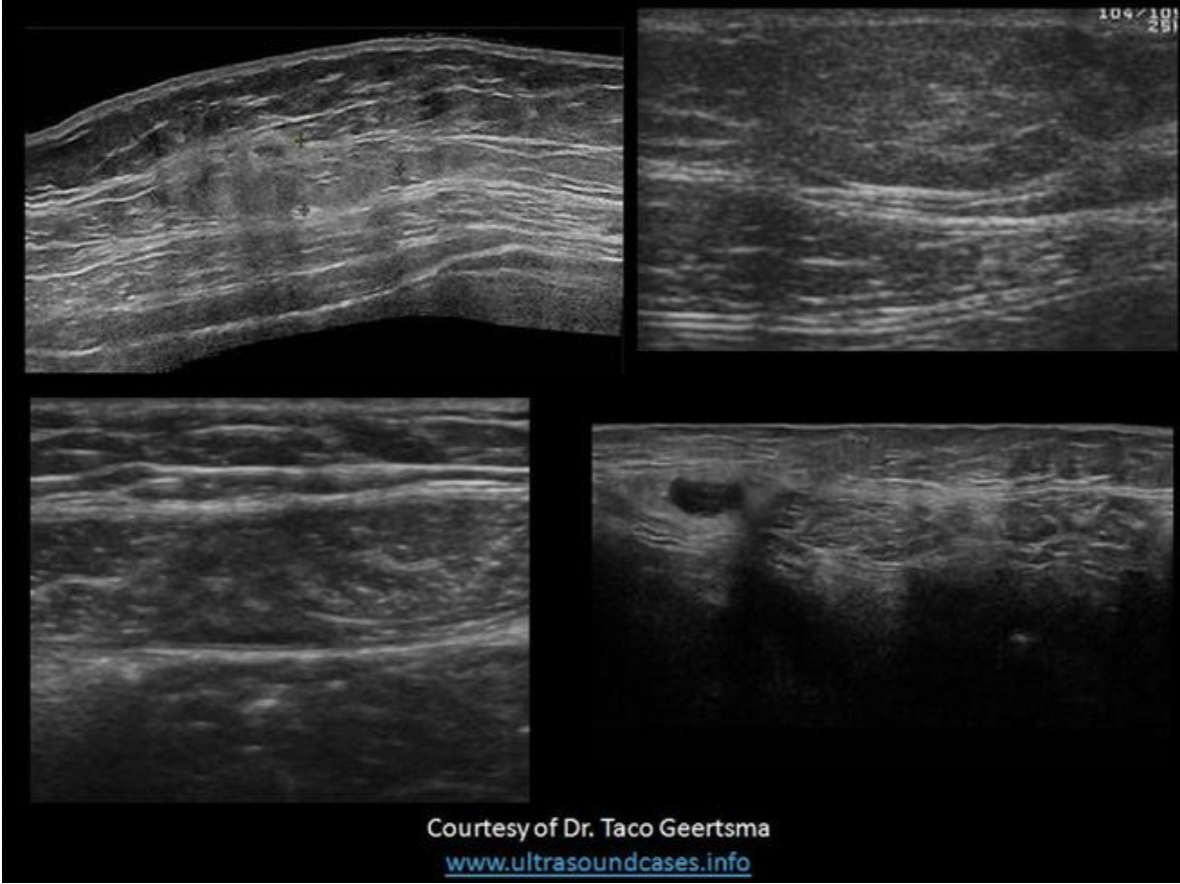

Find the rectus sheath hematoma

Top left is a benign mass with lobulated borders and the top right is a lipoma. Both are located in the subcutaneous tissues/fat between the skin and the anterior rectus sheath. The lipoma has smooth borders and an echogenicity similar to the surrounding fat.

The bottom right image demonstrates a spigelian hernia, between the right rectus abdominis and right oblique muscles.

The bottom left image demonstrates a hematoma in the rectus abdominis muscle, between the anterior and posterior rectus sheaths.

Find the lipoma

The top two images demonstrate solid masses that are superficial to the rectus abdominis muscle. Top left is a benign mass with lobulated borders and the top right is a lipoma. Both are located in the subcutaneous tissues/fat. The lipoma has smooth borders and an echogenicity similar to the surrounding fat.